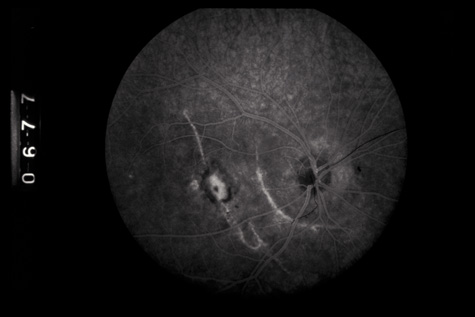

Commotio retinae (Latin, meaning retinal contusion) is a contrecoup injury. It can occur peripherally (Fig. 8) or centrally, in which case it is called Berlin's edema (Fig. 9). Immediately and for several hours after the trauma, the retina appears normal, although the patient may complain of decreased vision. Thereafter, the outer layers of affected retina become opaque. On fluorescein angiography, the opaque retina blocks background choroidal fluorescence, and in most cases there is no leakage into or under the retina (Fig. 10). For years, clinicians had difficulty explaining this blockage, because leakage is expected in conditions with edema. It was then shown in experimental animals and in human autopsy eyes that Berlin's edema is not true edema. The retinal opaqueness is the result of intracellular edema and fragmentation of the photoreceptor outer segments and intracellular edema of the underlying pigment epithelium. There is little or no intercellular fluid.66–69

Fig. 10. A: Commotio retinae in the macula. B: On the angiogram there is no leakage in the area of commotio retinae.

The visual acuity in commotio retinae varies from 20/20 to 20/400 and does not always correlate with the degree of retinal opacification. There is no known treatment. The prognosis is usually excellent except in cases with associated subfoveolar choroidal rupture and in cases with choroidal rupture with subfoveolar hemorrhage. Poor visual recovery can also be expected in cases with severe retinal pigment epithelial damage. Serous retinal detachment (Fig. 11) signals this condition, which can be confirmed by leakage of fluorescein into the subretinal space.70